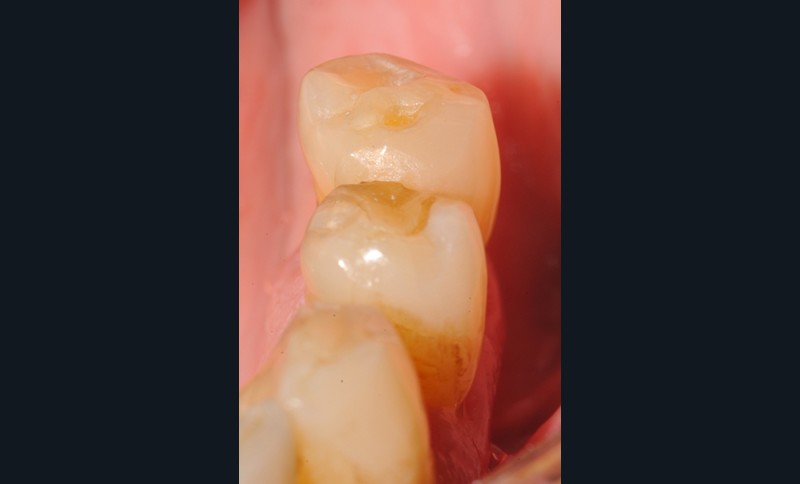

Aspect clinique et radiographique des lésions d’abrasion

Cliniquement, les lésions d’abrasion sont caractérisées par des facettes lisses, une absence de convexité et des bords à angles vifs. La flexibilité du ligament alvéolo-dentaire va entrainer un frottement au niveau des points de contact, qui peuvent se transformer en surfaces de contact (fig. 2c-d, 3 et 4b-c).

Radiographiquement, on observe une perte des cuspides et un aspect plan des faces occlusales (fig. 2a-b et 4a).